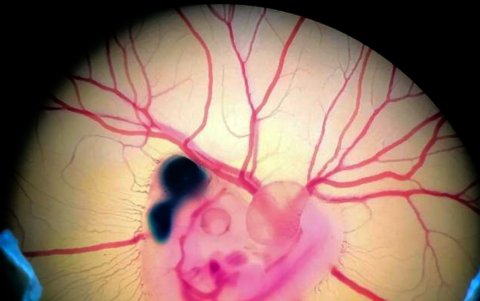

Embrión de pollo tras la manipulación experimental. Crédito: Fernando García-Moreno.